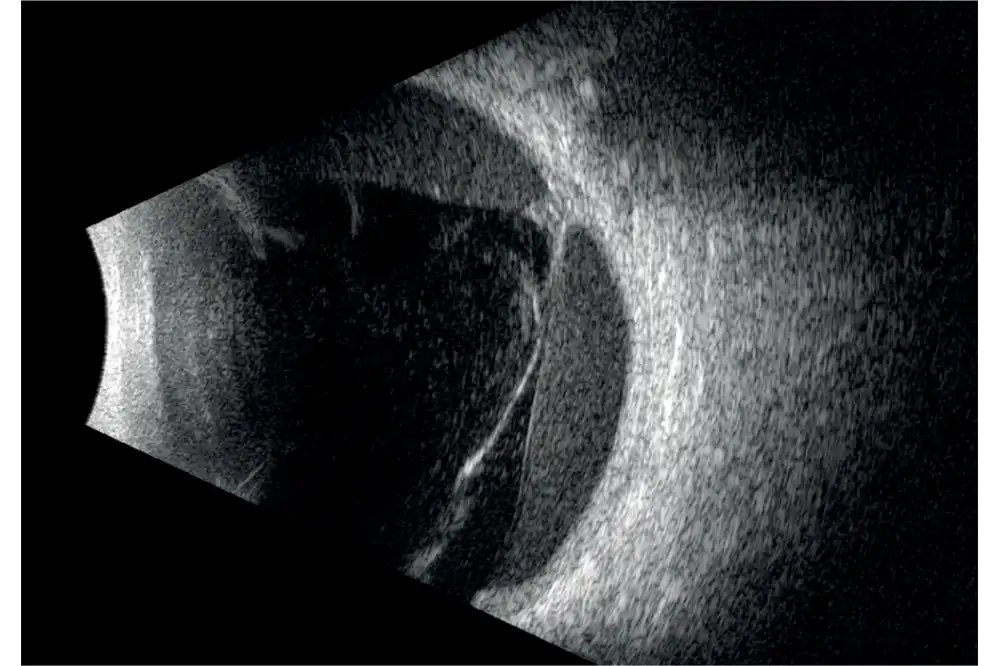

Het volledige oog is nu zichtbaar met een uitstekend detailniveau.

De ringtechnologie verdubbelt praktisch de scherptediepte. De 20 MHz-ringvormige sonde heeft een verlengde scherptediepte van 70%, waardoor het mogelijk is om pathologieën van het glasvocht, het netvlies en verder tegelijkertijd te observeren zonder concessies te doen aan de beeldresolutie.

- Verhoogde scherptediepte waardoor het gehele oog zichtbaar is.

- Hoge resolutie die het mogelijk maakt om van het voorste gedeelte van het glasvocht tot aan de wand te zien.